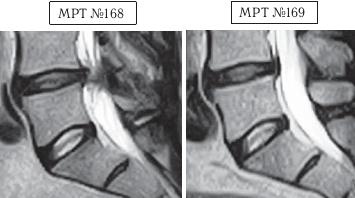

На МРТ № 168 наблюдается состояние поясничного отдела позвоночника: секвестрированная грыжа межпозвонкового диска в сегменте LIV-LV с разрывом задней продольной связки, отрывом фрагмента секвестра с его дорсальной миграцией, абсолютный стеноз спинномозгового канала. Такое состояние — последствия лечения протрузии межпозвонкового диска с применением хиропрактической техники манипуляций на позвоночнике (мануальная терапия).

На МРТ № 169 — состояние поясничного отдела позвоночника после лечения методом вертеброревитологии: отсутствие грыжи межпозвонкового диска в сегменте LIV-LV, отсутствие стеноза спинномозгового канала.